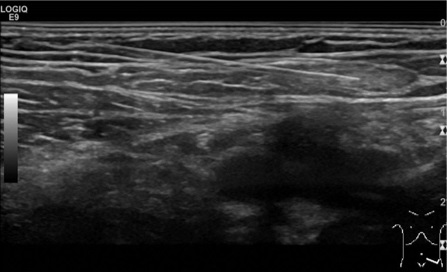

病例 53岁 女性;吞咽困难(weight loss) BMI 23 呼吸功能正常;胃镜发现胃腺癌,CT:T3NxM0 PET/CT:N0M0 MDT:新辅助化疗:FOLFOX4(x 4) 外科:Lewis-Santy pTNM:yT4N1M0 辅助 Chemo-radiation

乳糜胸消失

没再复发 No recurrence

术后21天出院